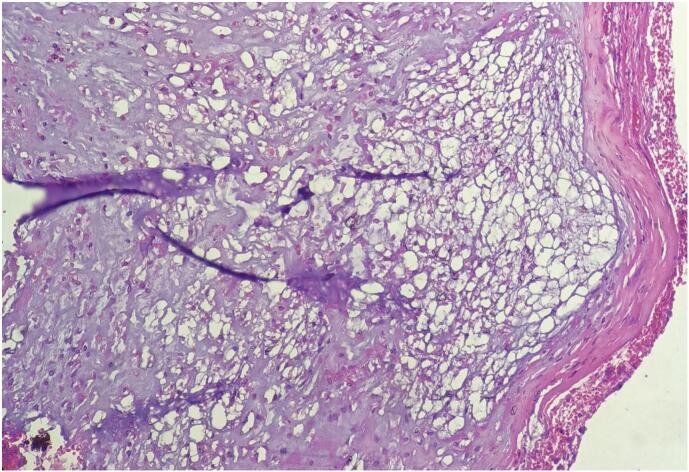

Here we present a 60 years old male patient presented with foul smelling nasal discharge, nasal obstruction and snoring of 2 years duration and Head CT scan was concluded to be advanced nasopharyngeal carcinoma but histopathology result turned out to be the uncommon nasopharyngeal chordoma. Therefore, he was treated with surgical excision and adjuvant radiotherapy.

Patient presentation usually varies by location; however, patients can be asymptomatic. CT and MRI are considered the initial modes of investigation, but histopathology is needed to confirm the diagnosis. Surgery is the primary mode of treatment with or without adjuvant chemoradiotherapy.

我们在此呈现一名60岁男性患者,有2年的恶臭鼻涕、鼻塞和打鼾症状,头部CT扫描诊断为晚期鼻咽癌,但组织病理学结果显示为罕见的鼻咽部脊索瘤。因此,他接受了手术切除及辅助放疗。

患者的表现通常因部位而异;然而,患者也可能无症状。CT和MRI被认为是初始检查方式,但确诊需要组织病理学检查。手术是主要治疗方式,可联合或不联合辅助放化疗。